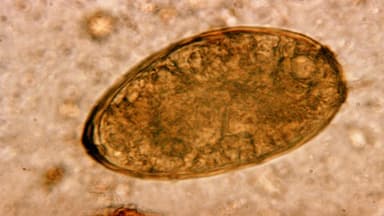

Ở giai đoạn đường mật, sán lá gan lớn cư trú và đẻ trứng trong đường mật, có thể gây tắc mật. Nội soi mật tụy ngược dòng có thể được sử dụng để chẩn đoán và kết hợp điều trị lấy sán qua nội soi. Hình ảnh nội soi mật tụy ngược dòng có hình giãn đường mật và hình khuyết trong lòng đường mật.